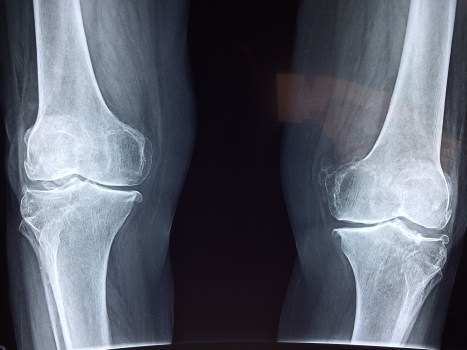

(not my knees)